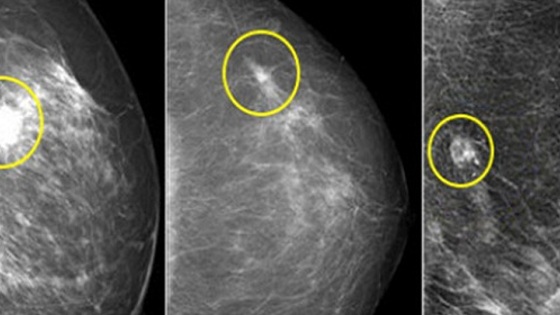

Онколог рассказала, что чаще всего рак можно заподозрить, если в груди наблюдается уплотнение, которое обычно не вызывает боли и не проявляется в общем состоянии. Однако при самостоятельном осмотре его можно обнаружить.

Поэтому врач рекомендовала женщинам регулярно проводить самопальпацию, ощупывая свою грудь и обращая внимание на любые необычные уплотнения или изменения, сообщает e1.ru.